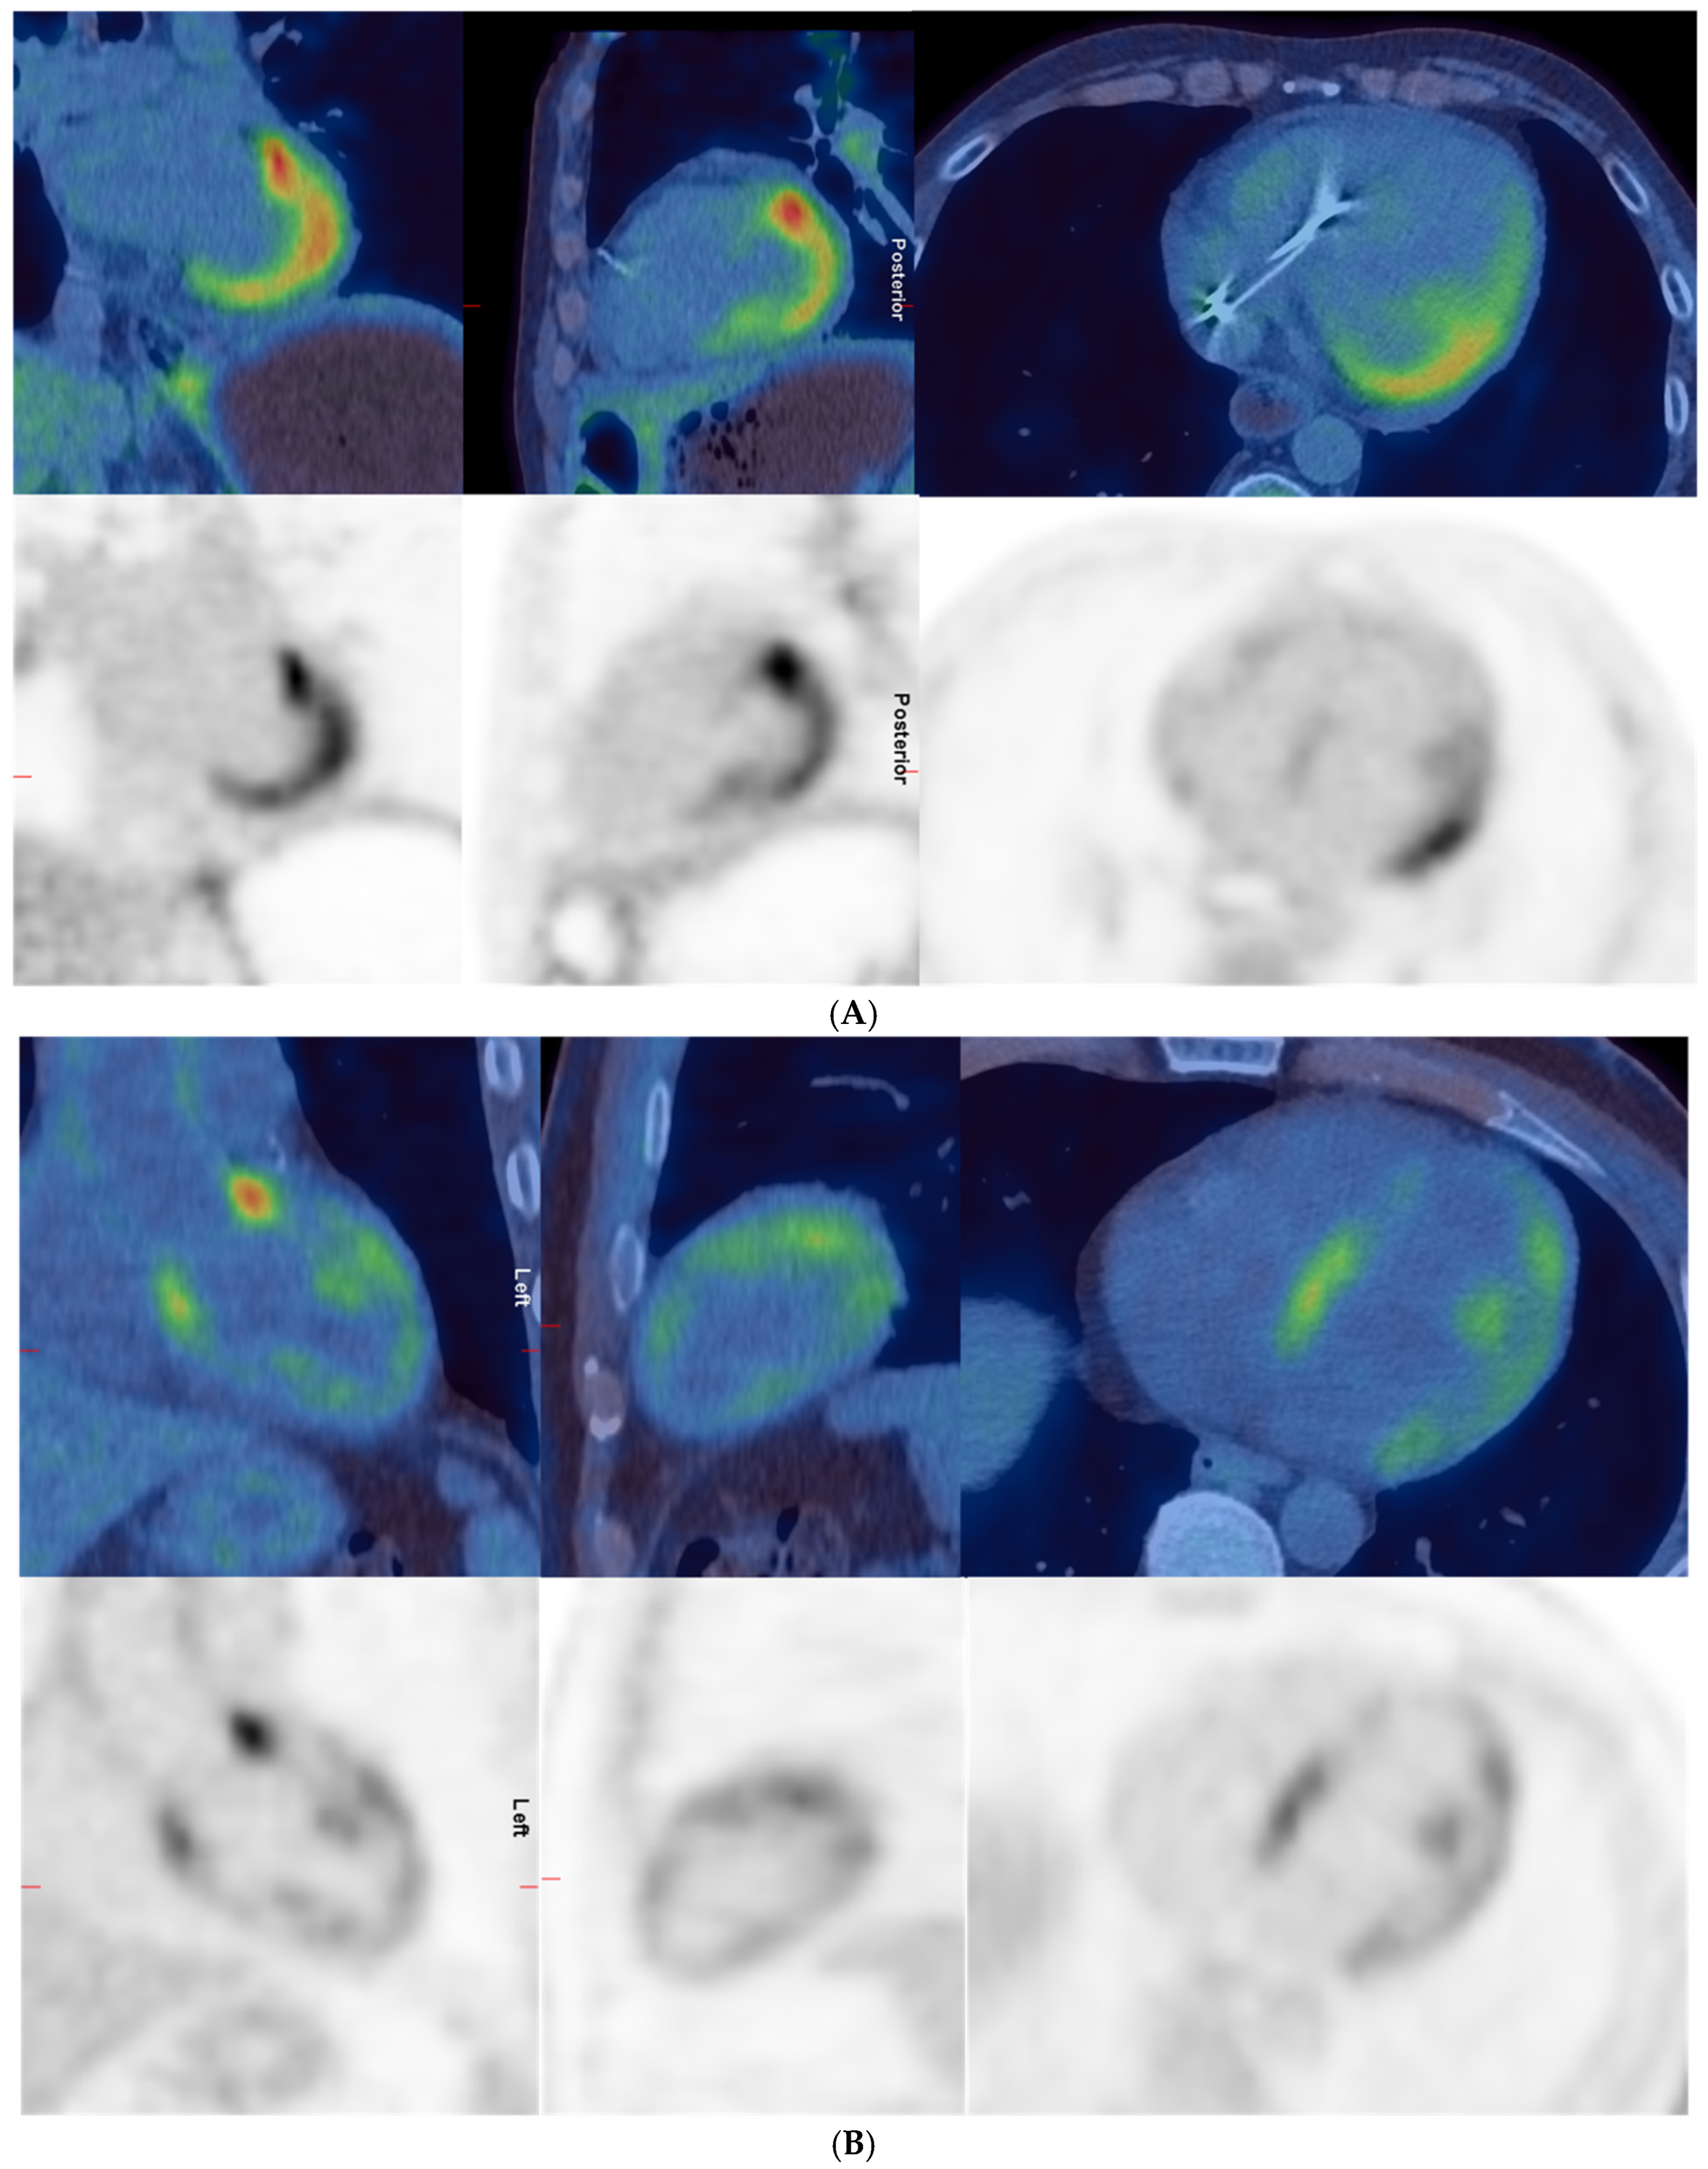

| 5 | 1 | Increased uptake in the heart and intense uptake in the lateral wall, apex, and anterolateral papillary muscle. Cardiac uptake could represent cardiac involvement by scleroderma or physiologic myocardial uptake. | Intense uptake in apex, lateral wall, and right ventricle. Moderate uptake in septum, anterior, and inferior walls. Indeterminate—likely negative. | 11.5 | 5 |

| 7 | 1 | Abnormal uptake in the heart with intense uptake in the base of septum and base of the lateral wall. More moderate uptake in the anterior aspect of the septum and lateral wall. Increased uptake in the LV papillary muscles. Could represent cardiac involvement by scleroderma. | Intense in base of septum and lateral wall, moderate in remainder of lateral and septal walls, moderate in right ventricle, intense anterior to AP trunk; likely physiological uptake. | 10.4 | 10.3 |

| 2 | Diffuse intense heterogeneous uptake in the LV and low-to-moderate uptake in the anterior and lateral walls of the RV. Uptake not significantly changed compared to previous scan. | Diffuse moderate uptake in left and right ventricles, greater than MBP. Likely not suppressed uptake; physiological rather than cardiac inflammation. | 9.6 | 9.6 | |

| 8 | 1 | Diffuse moderate-to-intense uptake in the LV and low-grade uptake in RV; could represent active cardiac myositis. | Moderate diffuse in left ventricle and low-grade in right ventricle; pattern likely physiological. | 7.4 | 5.5 |

| 2 | Intense diffuse homogeneous uptake in the LV and moderate diffuse homogeneous uptake in the RV; unchanged compared to previous scan. | Intense diffuse in left and right myocardium; likely physiological. | 19.5 | 17.7 | |

| 12 | 1 | Increased uptake in the LV, RV, and RA compatible with areas of inflammation due to cardiac involvement by scleroderma. Increased uptake in mediastinal nodes. Abnormal uptake in the larynx. | Moderate in LV lateral wall, base of anterior and inferior walls, low-grade in base of septum and right ventricle. Indeterminate—likely positive. | 7.1 | 2.5 |

| 2 | N/A | Intense diffuse in left myocardium and low-grade in right ventricle; likely physiological. | 11 | 8.2 | |

| 13 | 1 | Patchy myocardial uptake in LV, may represent active myocarditis. Low-grade uptake in hilar lymph nodes is likely inflammatory. | Moderate heterogeneous in left ventricle with intense in base of anterior wall. Indeterminate—likely positive. | 7.4 | 4.2 |